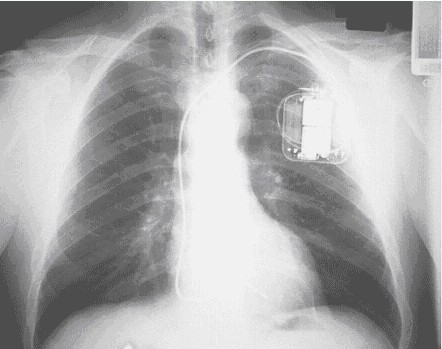

(三)除颤器植入

目前临床上应用除颤器均埋藏于患者胸前(图2),作为单极除颤系统的一个极,除颤器必须埋藏在左胸前。ICD胸前植入可埋于肌肉下囊袋或皮下囊袋,视患者胸前皮下组织而定,若患者较瘦,皮下脂肪少,可将ICD埋于肌肉下,对于皮下脂肪较多的患者,可将ICD埋于皮下囊袋。以往的ICD植入手术通常在手术室进行,由于非开胸除颤系统简化了手术过程,目前大多数在导管室进行,由心内科医生植入。

图2 经静脉植入ICD后的X片影像。